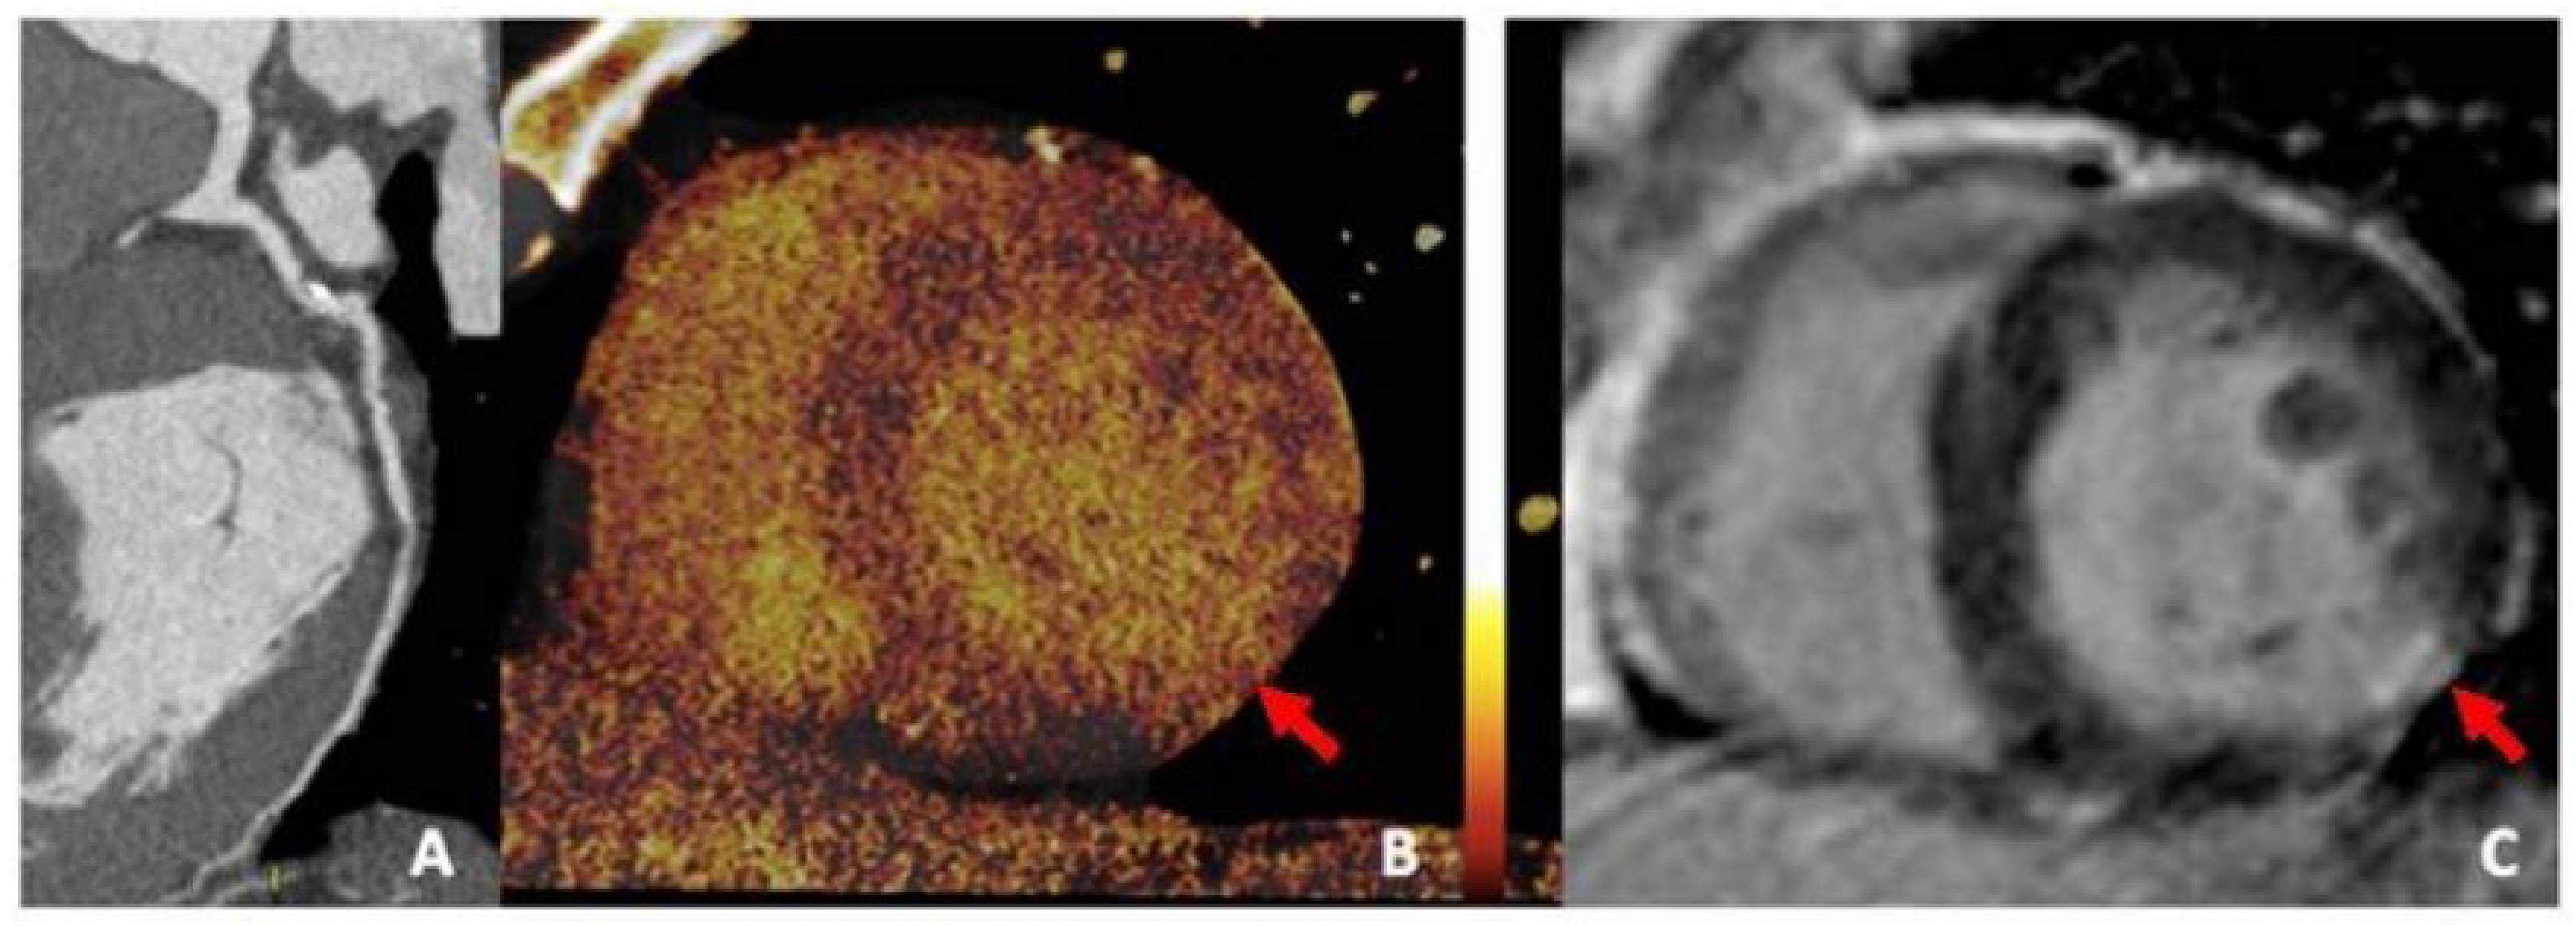

6.2. Positron Emission Tomography

The high spatial resolution and accuracy that imaging studies such as positron emission tomography (PET) (Figure 11) have, while utilizing fluorine isotopes to identify high-risk calcium plaques earlier in their progression, is better than CCTA because of the lower thresholds (200–500 µm) that the PET scan can operate on [48]. There is a relationship between 18F-NaF uptake and coronary calcification progression in stable CAD, as this molecular isotope represents a strong predictive marker for coronary artery calcification [56].

In addition to coronary artery disease, PET imaging utilizing 18F-NaF uptake has also been introduced in other vascular studies to examine other physical morphologies more effectively, including carotid atherosclerosis, abdominal aortic aneurysm (AAA) disease, aortic stenosis, bioprosthetic valve degeneration, and erectile dysfunction [57]. Lastly, the prognostic value of 18F-NaF uptake using PET-CT to assess coronary artery calcified plaques is currently being investigated through the ongoing prospective study, pioneered by the Prediction of Recurrent Events With 18F-Fluoride (PREFFIR) study [48].

Dual-energy CT (DECT) (Figure 13), also known as spectral CT, is another emerging imaging technique that provides high-quality anatomic information on CAC while enhancing plaque visualization and facilitating the accurate assessment of high-risk calcified plaques by combining information from both CT and the effective atomic number [61]. DECT enables the use of multiple virtual monoenergetic images to reduce blooming artifacts caused by highly dense calcifications, and it facilitates intracavity visualization by decreasing background noise, which is a limitation of CCTA [48,62].